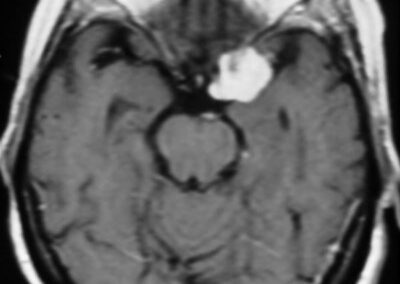

El diagnóstico se puede confirmar y el tumor localizar mediante:

• TAC cerebral

• RM cerebral

• Angiografía cerebral